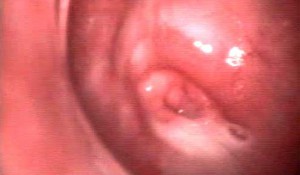

zervix_a